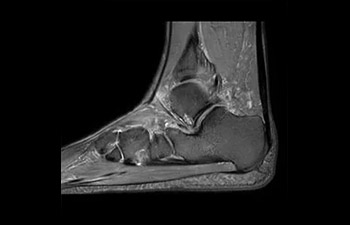

Sistema musculoesquelético

Tobillo

con Compressed SENSE